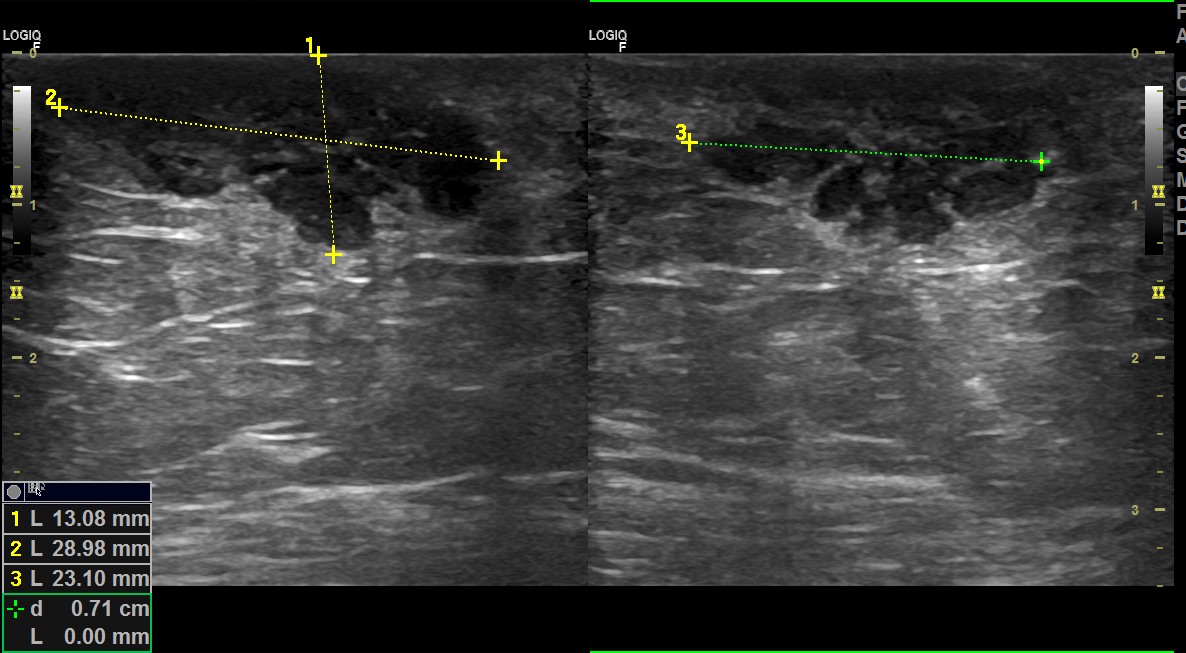

Hallazgos ecográficos

Tras ausencia de mejoría, realizamos ecografía programada: detectando una imagen sólida hipoecogénica, de bordes bien delimitados, con tractos fibrosos en su interior y con importante captación Doppler.

La ecografía cambia radicalmente la sospecha clínica y se remite a cirugía de forma preferente como masa sólida de rápido crecimiento a estudio y valorar resección.